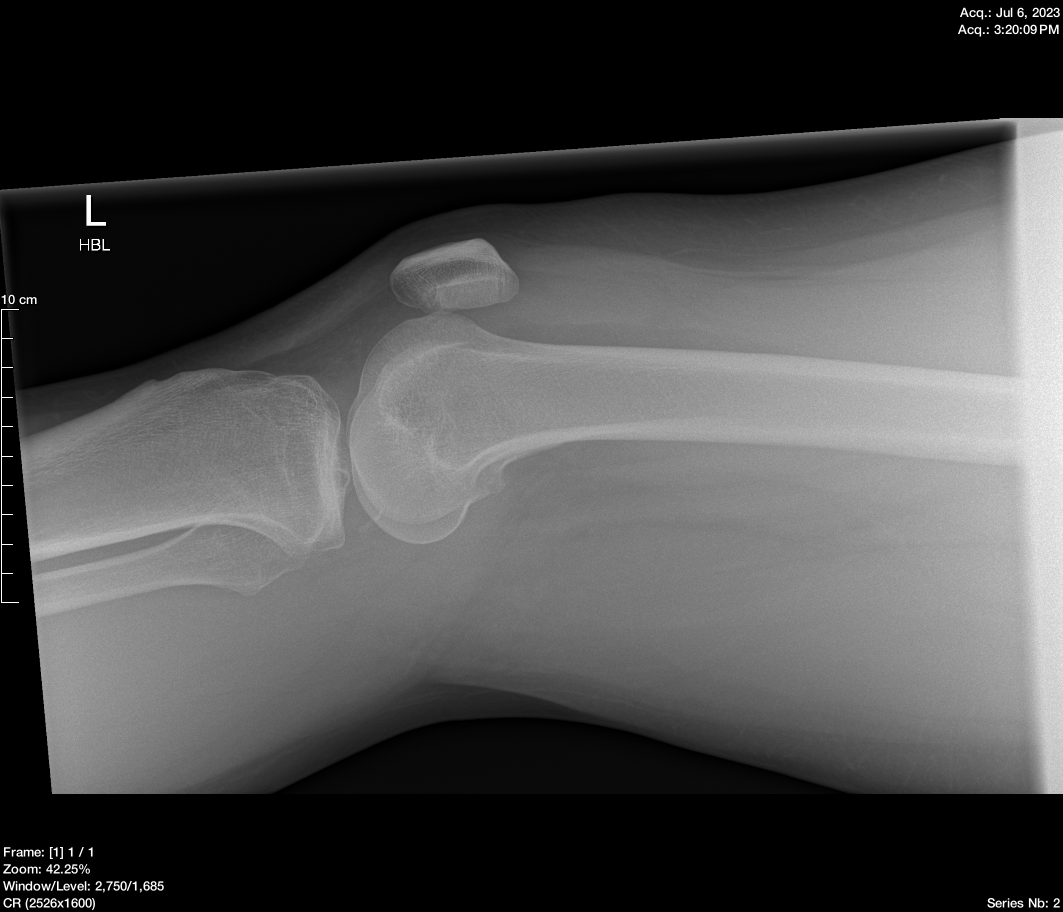

Sagittal

The report from the radiologist was that everything looked fine apart from a small piece of bone that had chipped off.

- Fracture/Dislocation: No acute fracture or dislocation identified.

- Joint Effusion: Moderate effusion in the suprapatellar bursa.

- Lipohaemarthrosis: Not present.

- Pellegrini-Stieda Lesion: Ossification at the proximal medial aspect of the medial femoral condyle, likely due to a previous avulsion fracture or ligamentous injury.

- Additional Density: Seen in the posterior femorotibial joint on the HBL view but not on AP view.

- Nature of Density: Unclear if degenerative or an old avulsion injury; not appearing acute.

At this point, I was a bit gutted they hadn’t found anything because I knew something was wrong. Because of clinical presentation, the doctor referred me to the orthopaedic department for further investigation.